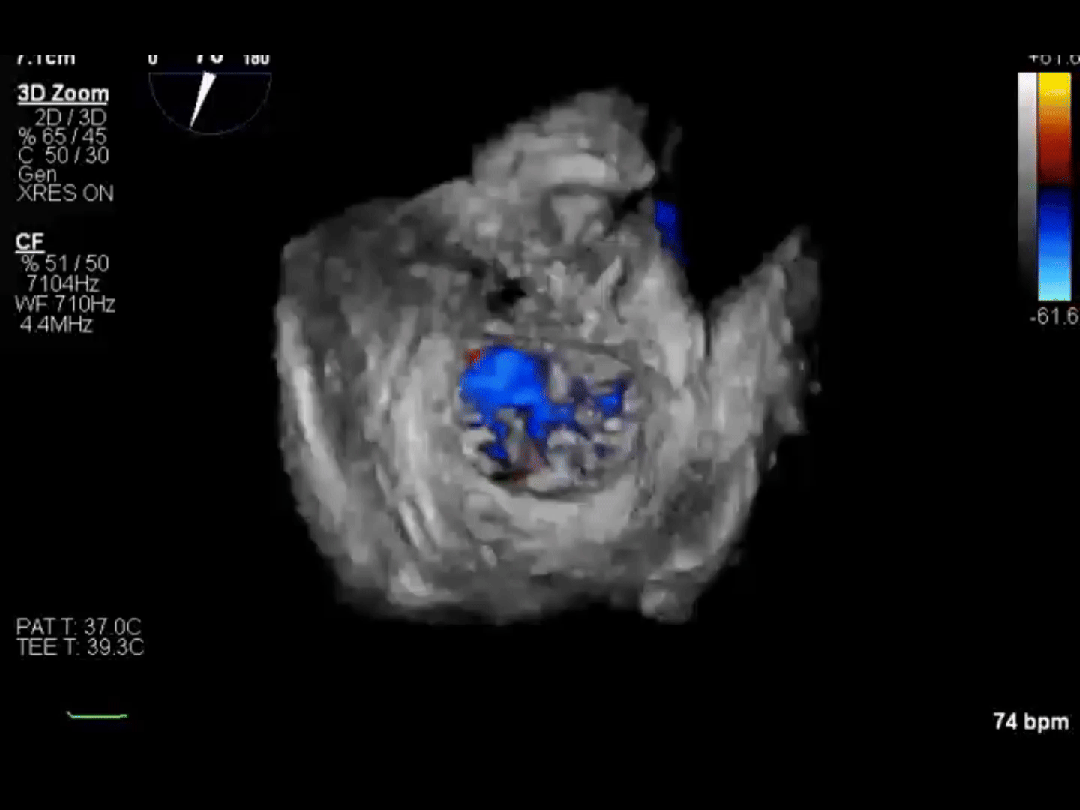

同样幸运的还有李爷爷。他因心脏二尖瓣脱垂导致血液严重反流,随时可能发生心衰。经过评估,医生为他选择了经导管二尖瓣钳夹术(TEER)。

手术中,医生通过大腿静脉送入特制夹子,在超声引导下精准夹合脱垂的瓣叶。整个手术不到 1 小时,李爷爷原本关不牢的「心门」变得「严严实实」,术后反流明显减少,充分彰显了团队的技术实力。